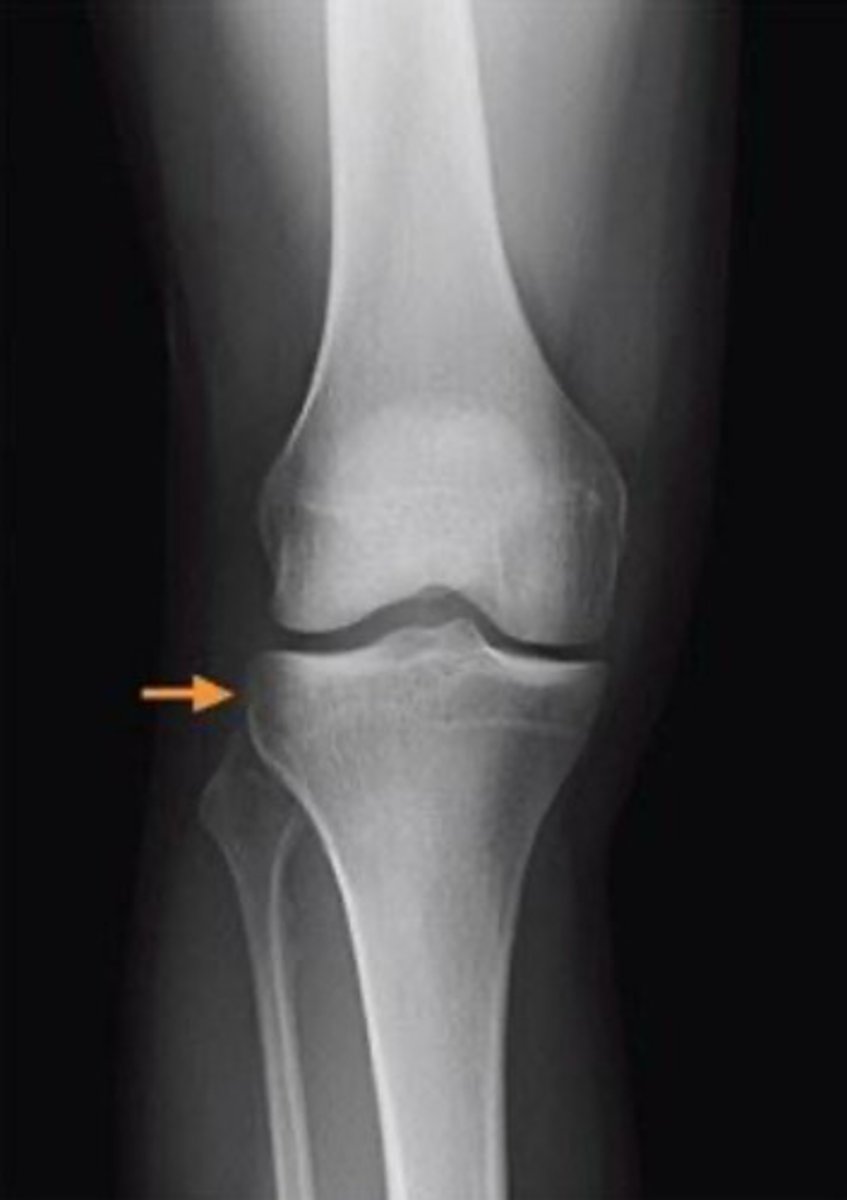

what radiograph view is this image in?

anteroposterior

3 multiple choice options

what is indicated by the orange arrow in this image?

segond fracture